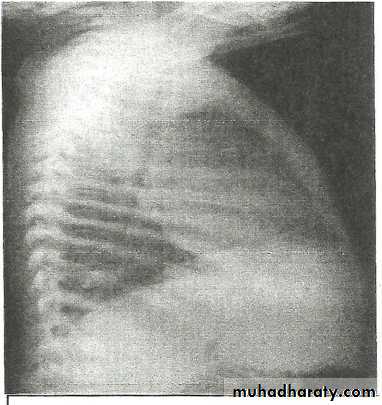

Pleural Effusion on Chest Radiographs.

Posteroanterior (A) and lateral (B) chest radiographs demonstrate the typical meniscoid appearance (arrows) in a patient with a left pleural effusion

Hydropneumothorax.

When fluid and air are present in the pleural space on an upright chest x-ray, a perfectly straight horizontal line will extend all the way from the spine to the edge of the pleural cavity. In this patient, a loculated right basilar hydropneumothorax is present.

The air/fluid interface is easily seen (arrows). If this were a lung abscess, the air/fluid level would be very unlikely to extend all the way from the medial to the lateral aspect of the hemithorax.